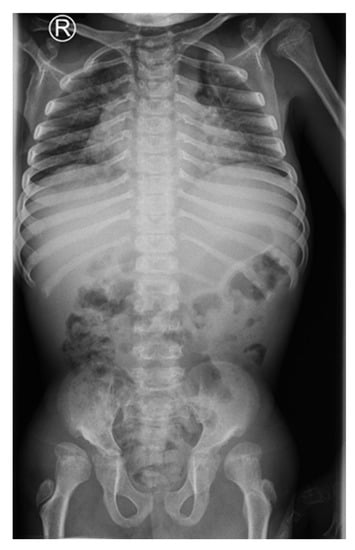

A 15-year-old boy suffering from SWS was born from the third pregnancy of nonconsaguine young and healthy parents as a hypotrophic infant with a perinatal risk factor which included intrauterine growth retardation and asphyxia. Complex phenotypic dysmorphic features were observed at birth. The phenotype of our patient includes multiple facial and skeletal disorders: midface retrusion, prominent forehead, frontal bossing, shallow orbits, downslanted palpebral fissures, narrow nasal bridge, large filtrum, micrognathia, small hands with short metacarpal bones and short distal phalanges of fingers with consequent brachydactyly, knee flexion contracture, pseudoarthrosis, calcaneovalgus deformity, thoracic scoliosis, lumbar hyperlordosis, coxa valga, skeletal dysplasia, pectus carinatum, generalized hypotonia, global developmental delay, cognitive impairment, complete lack of adipose tissue with consequent pseudohypertrophy of muscles, bilateral cataracts and progeroid facial appearance (Figure 1 and Figure 2). As a part of the syndrome, an extremely short stature, body weight of 15 kg and body height of 100 cm were observed.

Figure 2. Dysplastic changes of the acetabulum, coxa valga, lucencies of the proximal femora, flattened vertebral bodies (platyspondyly), 11 years of age.